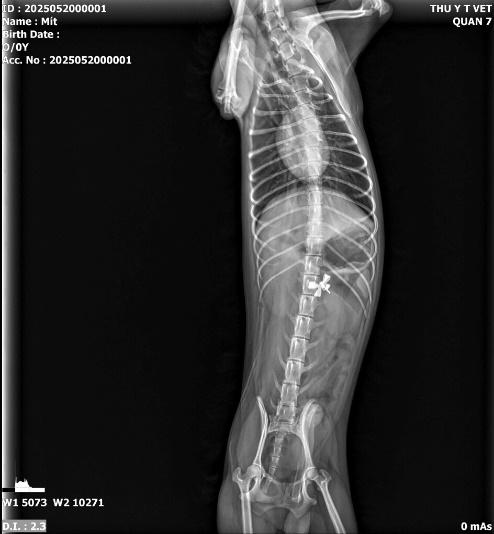

Đây là ứng dụng phổ biến nhất của X-quang. Từ những va chạm nhỏ đến các tai nạn giao thông nghiêm trọng, việc kiểm tra cấu trúc xương là bắt buộc. Dịch vụ X-quang giúp bác sĩ xác định:

• Vị trí gãy xương chính xác (xương đùi, xương chậu, xương trụ...).

• Kiểu gãy: Gãy cành tươi, gãy phức tạp, hay gãy hở.

• Độ lệch của các đầu xương để tiến hành phẫu thuật kết hợp xương (đóng đinh, bắt vít) hiệu quả nhất.

.jpeg)

Hình ảnh: gãy xương trụ và xương quay trước